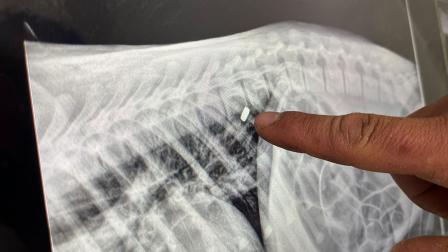

Frente a las primeras radiografías del ejemplar, el biólogo detalló que la bala entró por la vertebra lumbar provocando el daño en las extremidades, para después alojarse en la costilla del oso negro.

“Por suerte, no perdimos mucho la conformación de la vértebra, y la bala se encapsuló, por lo que no representa ningún problema, y decidimos dejarla ahorita ahí”, señaló.